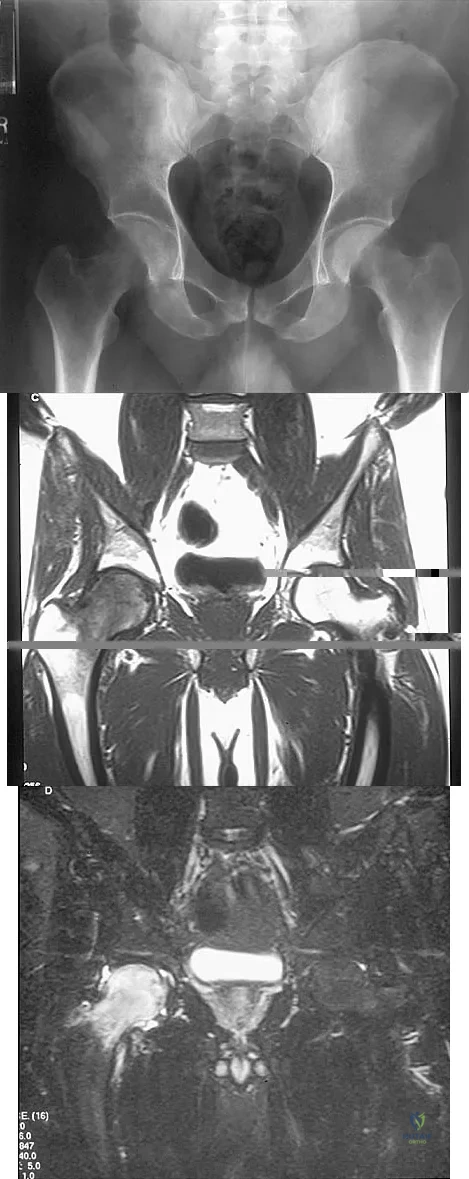

Question 28

Figures 10a through 10c show the plain radiograph and MRI scans of a 41-year-old man who has right hip pain. What is the most likely diagnosis?

Explanation